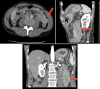

Intussusception is defined as the invagination of one segment of the bowel into an immediately adjacent segment of the bowel. Idiopathic ileocolic intussusception is the most common form in children and is typically managed with nonoperative reduction via pneumatic and/or hydrostatic enemas. In the adult population, intussusception is uncommon and occurs more often in the small intestine than in the colon. It is associated with lead point pathology in most symptomatic cases presenting as bowel obstruction. When lead point pathology is present in adult small bowel intussusception, it is usually benign, though when malignant it is most frequently due to diffuse metastatic disease, for example, melanoma. In contrast, adult ileocolic and colonic intussusception lead point pathology is most frequently primary adenocarcinoma when malignant. The diagnosis is typically made intraoperatively or by cross-sectional imaging. With increasingly frequent CT/MRI of the adult abdomen in the current era, transient and/or asymptomatic intussusceptions are increasingly found and may often be appropriately observed without intervention. When intervention in the adult population is warranted, usually oncologic bowel resection is performed due to the association with lead point pathology.